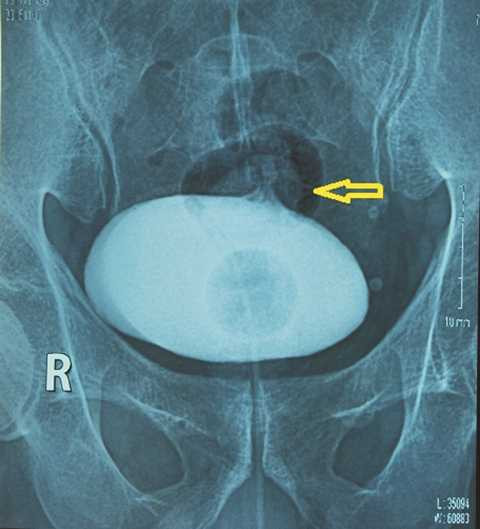

Chụp bàng quang bơm thuốc cản quang tan trong nước thấy thuốc đi vào đại tràng. Chụp đại tràng có thuốc cản quang không tan trong nước thấy thuốc vào bàng quang. Chụp CT bụng phát hiện có khối viêm dính từ đại tràng chậu hông vào bàng quang.

| Chụp phim Cystography thấy thuốc ra ngoài bọng đái |